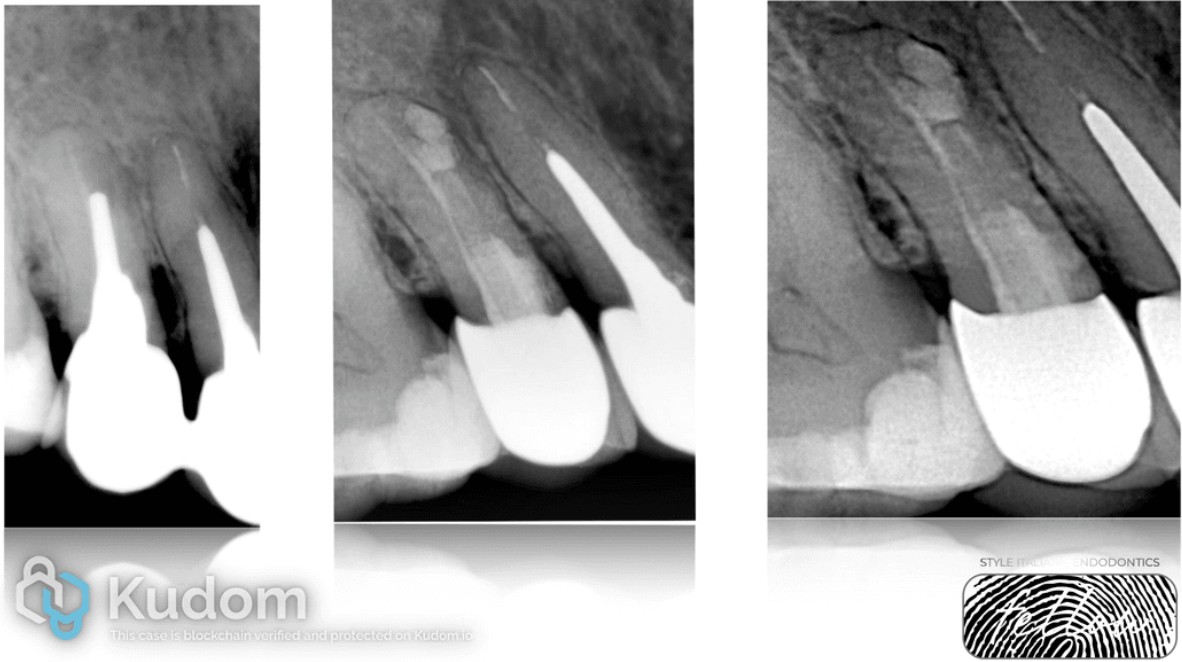

Fig. 3

The absence of a ferrule, perforation in the apical portion of the root, and the inability to perform adequate endodontics and prosthodontics on this tooth led to the only option being a plan to replace the tooth with an implant.

Fig. 4

However, considering the patient's life factors, the decision was made to save this tooth and choose a patient-oriented treatment plan. The program to save this tooth began with sealing the perforation using MTA. The Crown-Tissue aspect became the primary salvage strategy for this clinical case

Fig. 5

Crown-Tissue is the main salvage strategy for this clinical case. Immediately after the repeated endodontic treatment, a temporary restoration was fabricated. After 8 days, closure of the fistulous tract, absence of symptoms, and stabilization of the soft tissues are observed